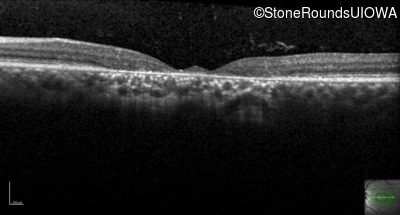

Age at visit: 29 years

This 29-year-old man had good vision until his early 20's. at which time he began to experience a slow reduction in his acuity. His driver's license was restricted at age 27.

Age at visit: 29 years (Visit 2)